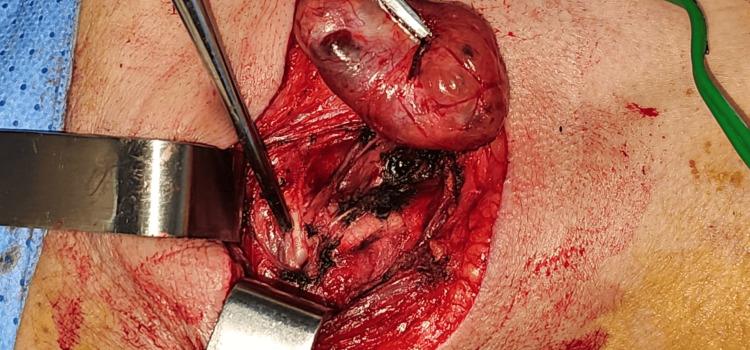

术中,肿块位于颈动脉分叉处,很容易从颈动脉血管(颈内动脉和颈外动脉)上剥离出来,没有任何血管损伤,并保留了下颅神经(迷走神经、舌下神经、舌咽神经)(图2)。

图2 术中拍摄的照片显示,在保留所有血管和神经的情况下,成功分离了肿块